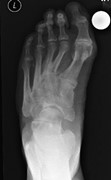

An additional middle cuneiform?

S.D. Brookes-Fazakerley and others

Journal of Surgical Case Reports, Volume 2015, Issue 7, July 2015, rjv076, https://doi.org/10.1093/jscr/rjv076